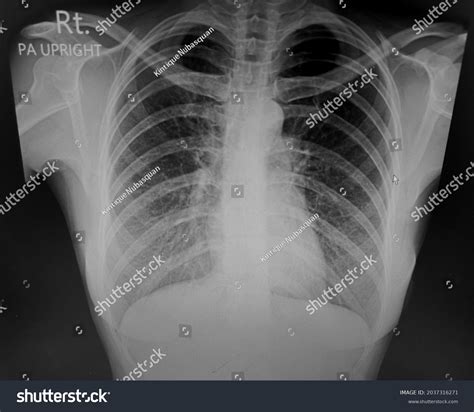

What Does a Normal Lung X-ray Look Like?

A normal lung X-ray typically shows clear lung fields with no signs of inflammation, infection, or other abnormalities. The lungs appear black due to the air they contain, while the heart and other structures appear white. The diaphragm, the muscle that separates the chest from the abdomen, is also visible and should be at a normal level.

Here are some key features of a normal lung X-ray:

• Clear lung fields with no opacities or infiltrates.

• Normal heart size and shape.

• Visible costophrenic angles (the angles where the ribs meet the diaphragm).

• No pleural effusions (fluid accumulation around the lungs).

• Normal vascular markings.